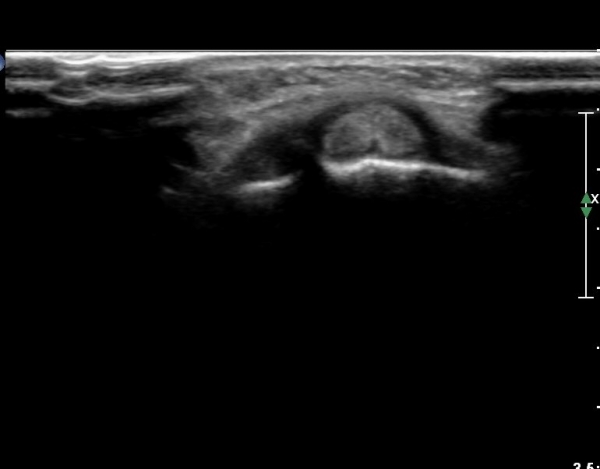

¼Õ¸ñ µî Áß¾Ó¿¡¼­ ¼Õ°¡¶ô ½ÅÀü°Ç Á¾´Ü¸é °Ë»ç¿¡¼­ ƯÀÌ ¼Ò°ßÀ» º¸ÀÌÁö ¾Ê´Â´Ù(»çÁø 1)